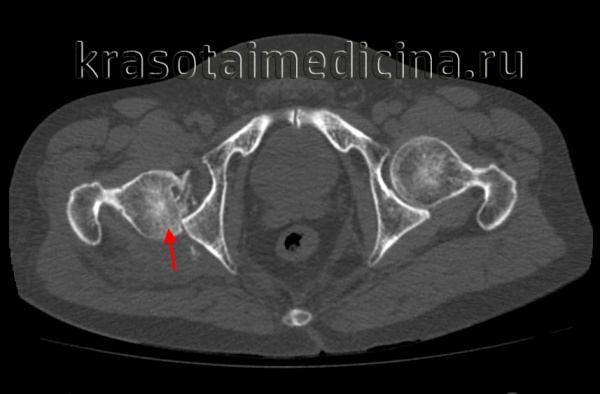

(Слева) КТ в передне-задней проекции, объемная 3D реконструкция: определяется задний вывих головки бедренной кости. КТ выполняется перед закрытой репозицией только если она оказалась неудачной. КТ позволяет оценить положение смещенных осколков, препятствующих репозиции.

3. КТ при вывихе бедра:

• Смещение головки бедренной кости

• Сопутствующие состояния:

о Переломы стенки вертлужной впадины четко определяются

о Трещина или вколоченный перелом головки бедренной кости:

- Аналог перелома Хилла-Сакса при суставно-плечевом вывихе

о Внутрисуставные костные осколки:

- Могут помешать закрытой репозиции

(Слева) КТ, аксиальный срез: в данном вывихе, репозиция которого возможна только под общей анестезией, визуализируется головка бедренной кости, вколоченная в заднюю губу вертлужной впадины.